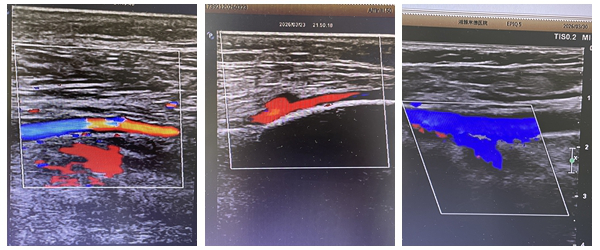

入院后,急诊科迅速启动急危重症救治流程,神经内科第一时间介入评估。经完善相关检查,显示患者右侧额颞叶软化灶可能、脑萎缩;双下肢动脉内-中膜增厚并多发斑块形成,左侧股静脉及股浅静脉起始部血栓形成,同时D-二聚体等凝血指标异常升高,属于高龄高危病例。

下肢静脉血栓若不及时干预,血栓脱落极易引发肺栓塞,危及生命。为最大程度降低风险、确保救治安全与效果,神经内科副主任医师胡鹏飞牵头多学科团队会诊,综合研判后为其制定了个性化治疗方案,严防血栓脱落风险。治疗期间,医护团队精准把控用药剂量,密切监测生命体征与肢体恢复情况。经规范治疗与精心护理,患者左下肢疼痛、肿胀明显消退,活动能力逐步恢复。复查超声显示左侧股静脉血流通畅,血栓得到有效控制,各项指标趋于正常,目前可自主完成简单活动。